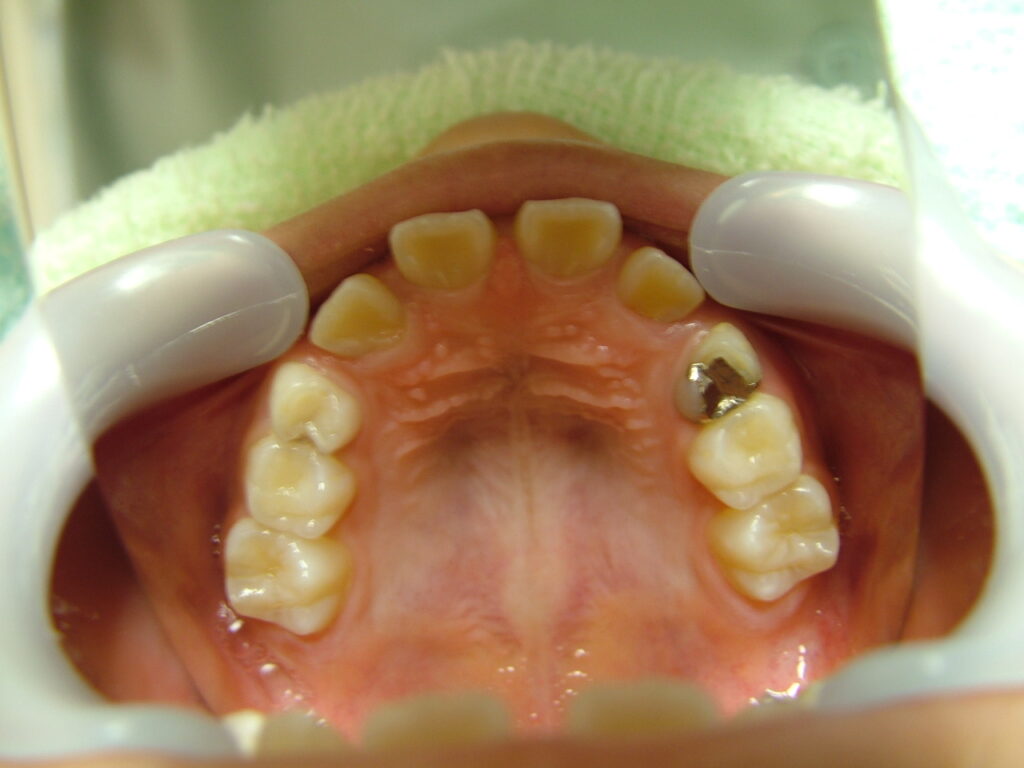

治療前

概要

- 初診:2016年、9歳女児

- 主訴:出っ歯と歯の隙間がきになる。

- 診断:2級過蓋咬合、上下永久歯(犬歯)萌出スペース不足

- 治療方針:非抜歯で行う。虫歯予防(フッ素)、歯磨き指導、上下拡大床→咬合関係改善のツインブロック(2級→1級関係へ)→マウスピース矯正→下親知らずの抜歯、保定→メンテナンス